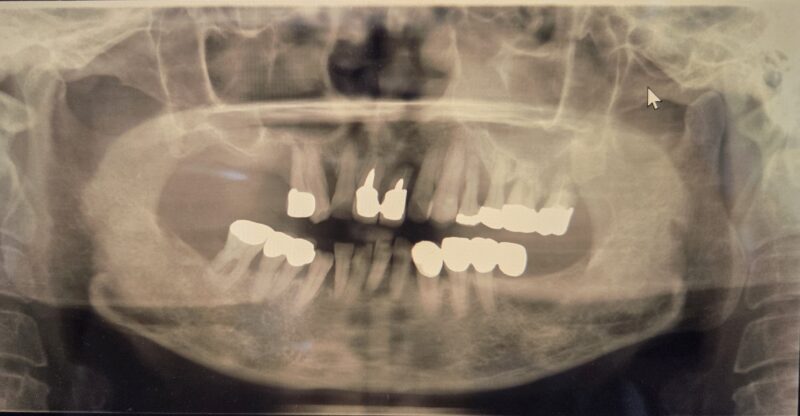

■ 当時の状態(2005年)

歯ぐきの病気が進み、歯を支える骨も減っていました。

噛む力は前歯に集中していて、奥歯がないため、

全体がどんどん壊れていく方向に向かっていました。

見た目を整えるだけの治療では、もう間に合いません。

ここでしっかり立て直さなければ、

近い将来すべての歯を失う危険がありました。